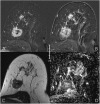

Due to its superior sensitivity, breast MRI (bMRI) has been established as an important additional diagnostic tool in the breast clinic and is used for screening in patients with an elevated risk for breast cancer. Breast MRI, however, is a complex tool, providing multiple images containing several contrasts. Thus, reading bMRI requires a structured approach. A lack of structure will increase the rate of false-positive findings and sacrifice most of the advantages of bMRI as additional work-up will be required. While the BI-RADS (Breast Imaging Reporting And Data System) lexicon is a major step toward standardised and structured reporting, it does not provide a clinical decision rule with which to guide diagnostic decisions. Such a clinical decision rule, however, is provided by the Kaiser score, which combines five independent diagnostic BI-RADS lexicon criteria (margins, SI-time curve type, internal enhancement and presence of oedema) in an intuitive flowchart. The resulting score provides probabilities of malignancy that can be used for evidence-based decision-making in the breast clinic. Notably, considerable benefits have been demonstrated for radiologists with initial and intermediate experience in bMRI. This pictorial essay is a practical guide to the application of the Kaiser score in the interpretation of breast MRI examinations.

Teaching points: • bMRI requires standardisation of patient-management, protocols, and reading set-up. • Reading bMRI includes the assessment of breast parenchyma, associated findings, and lesions. • Diagnostic decisions should be made according to evidence-based clinical decision rules. • The evidence-based Kaiser score is applicable independent of bMRI protocol and scanner. • The Kaiser score provides high diagnostic accuracy with low inter-observer variability.